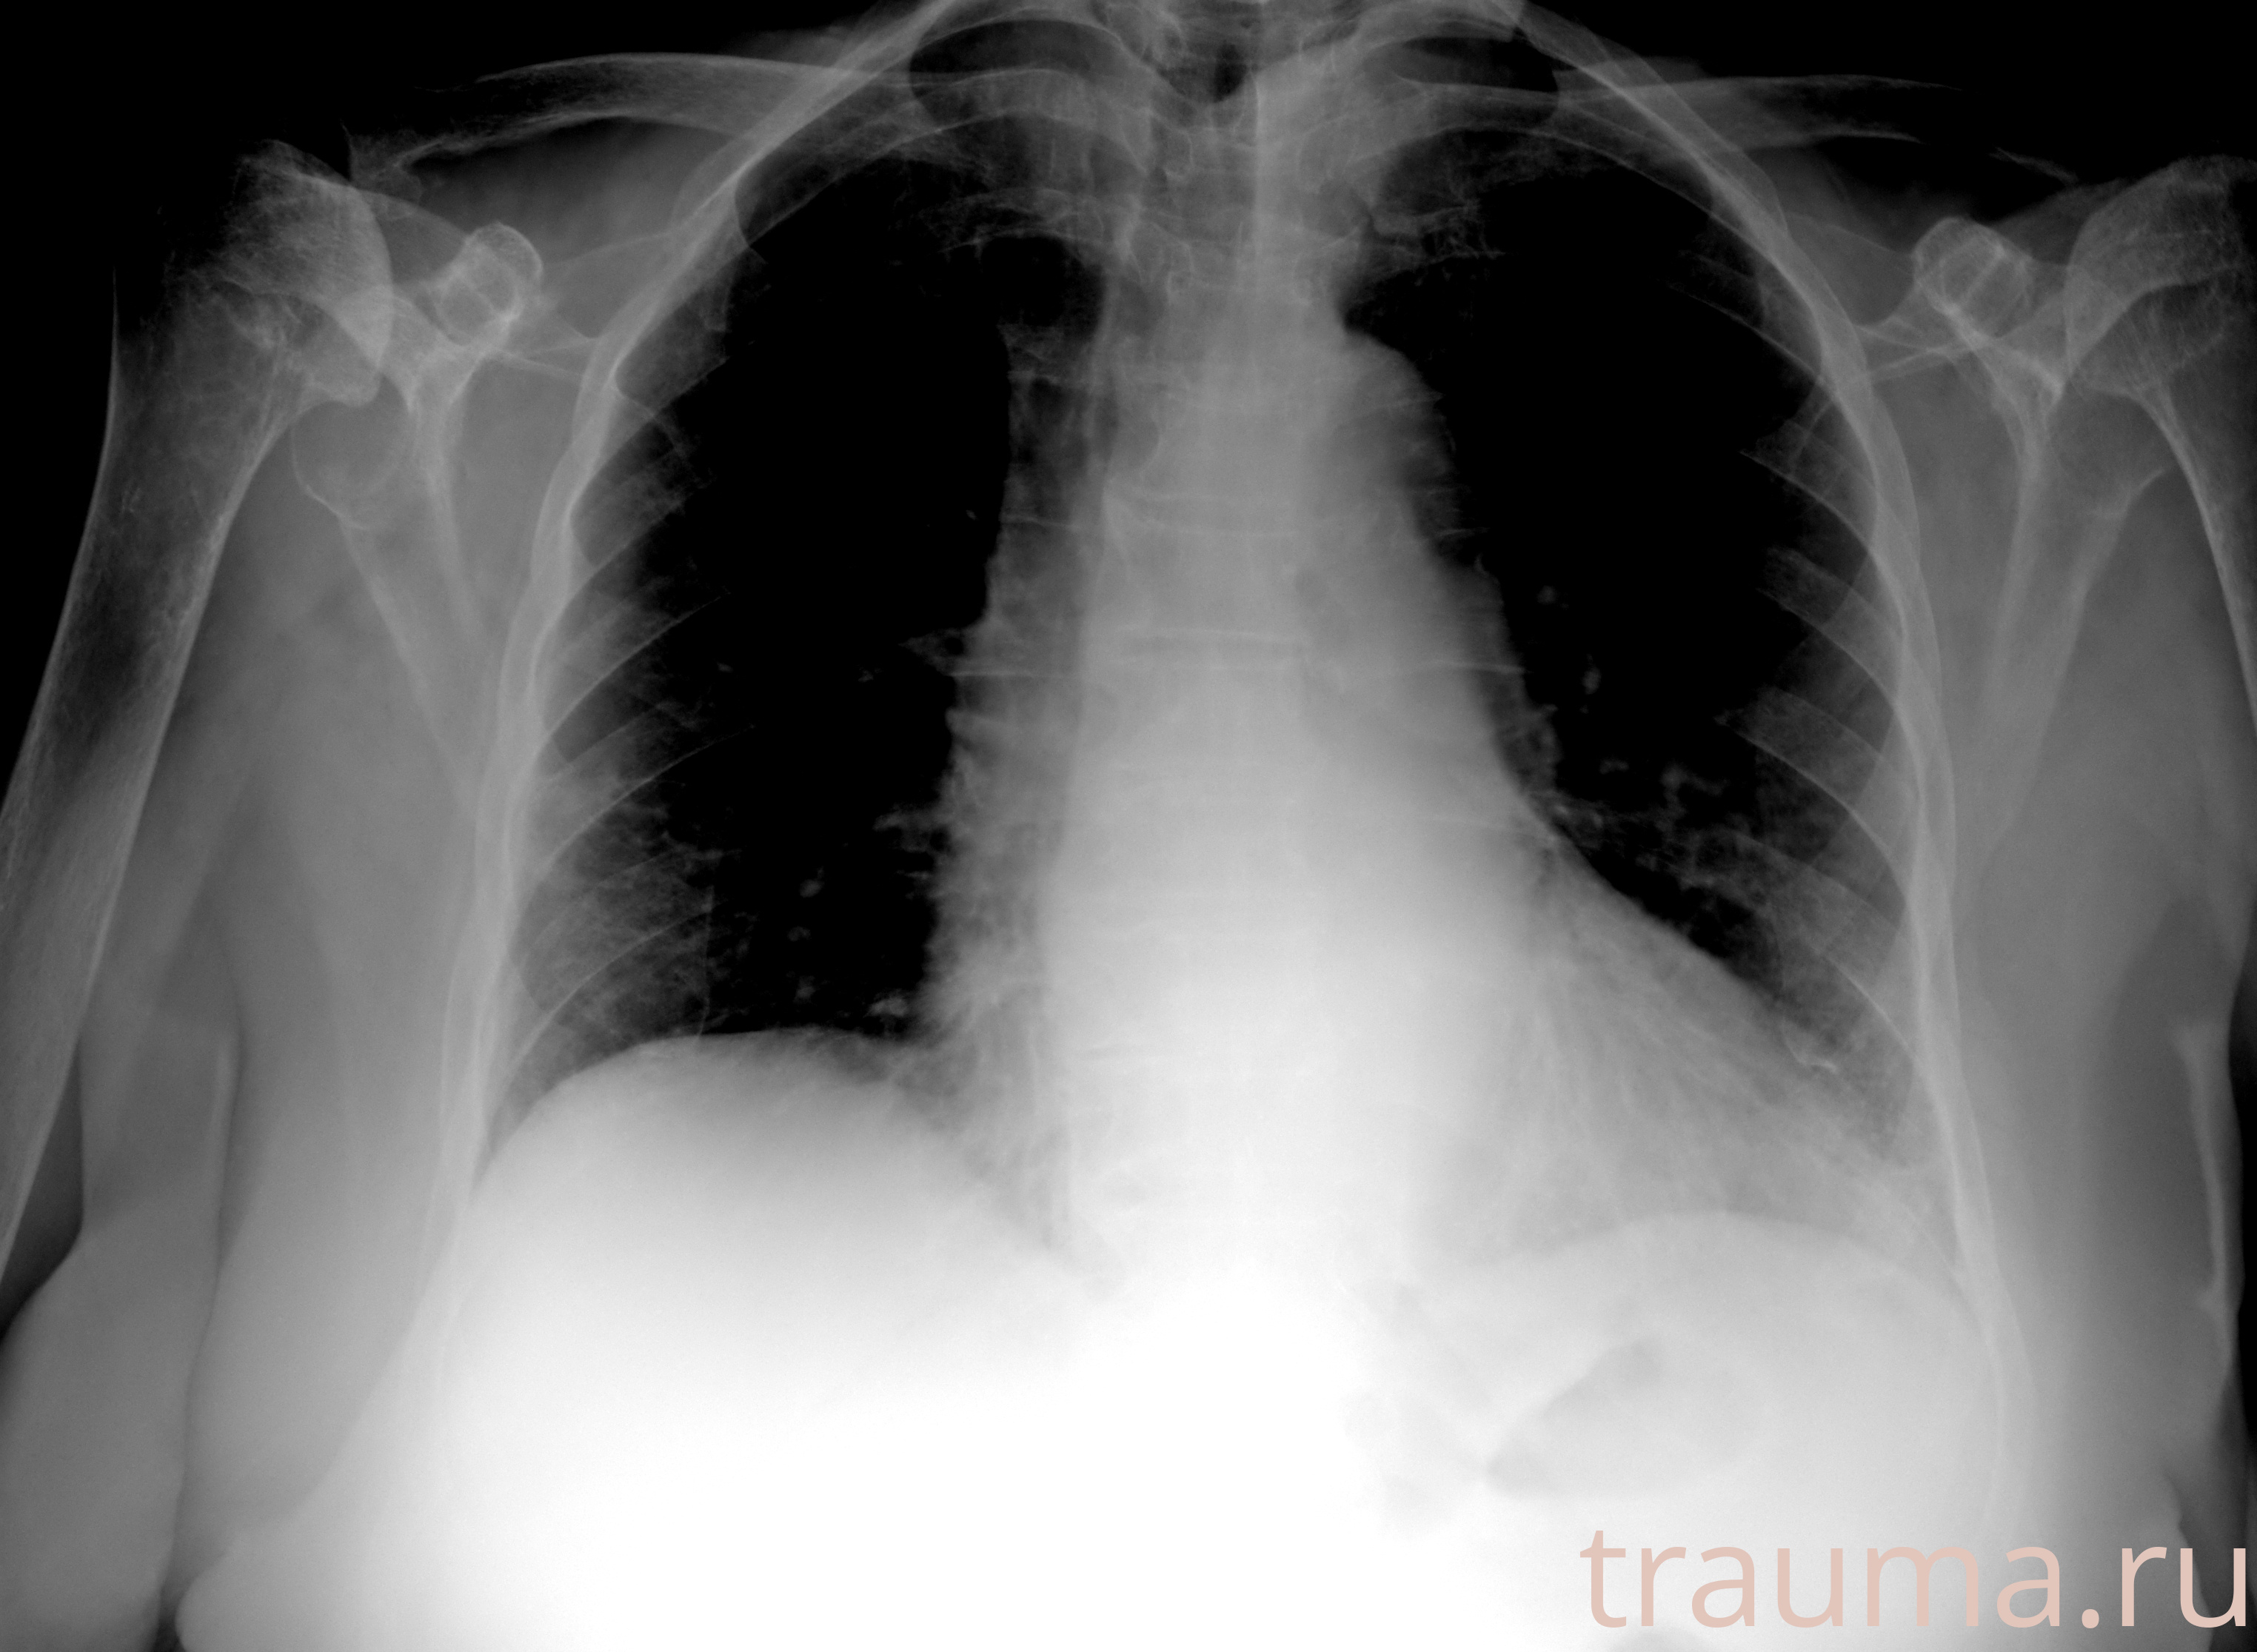

Рентгенограммы

Рентген на дому: по вашему адресу приезжает врач-рентгенолог, травматолог-ортопед с мобильным рентгеновским аппаратом, проводит диагностику травмы или заболевания, делает необходимые рентгенограммы, дает рекомендации по дальнейшему лечению. Получить качественные снимки в домашних условиях возможно благодаря уникальной методике, разработанной МосРентген Центром для института  Склифосовского